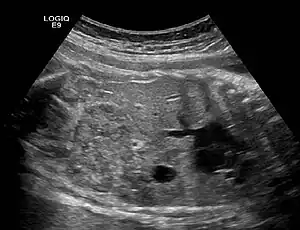

Ectopic kidney describes a kidney that is not located in its usual position. It results from the kidney failing to ascend from its origin in the true pelvis or from a superiorly ascended kidney located in the thorax.[1]